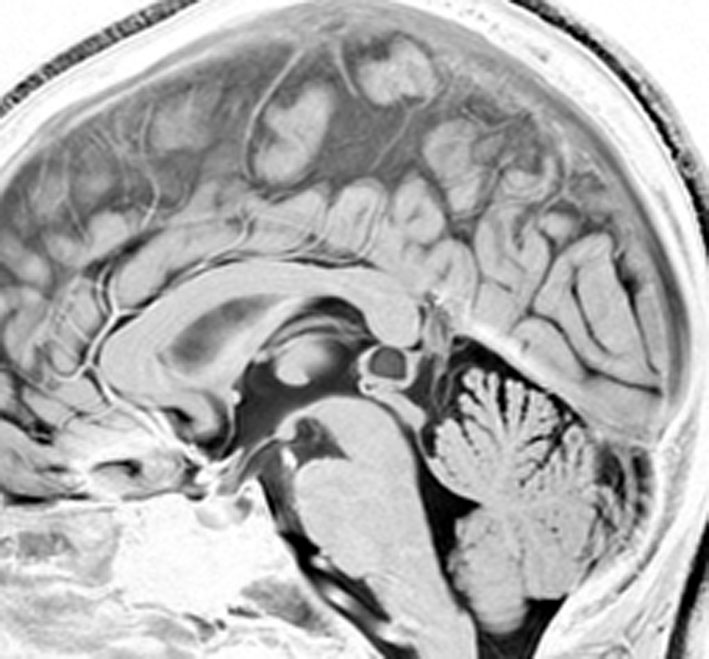

これも成人女性に偶然見つかった松果のう胞です。少し大きめですが,何も治療する必要はありません。中脳水道という所が狭くなっていますが,はっきり閉塞するまでは治療はしません。左がT1強調画像で黒っぽく見えます。右はT2強調画像で白く映っています。